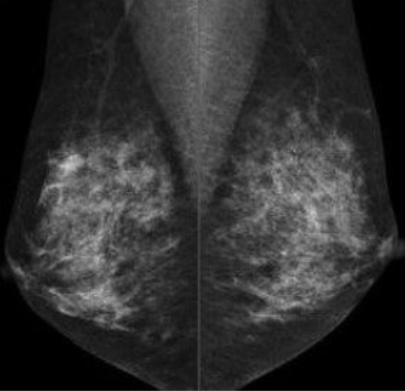

- 40대~: 매년 유방촬영술(mammography)